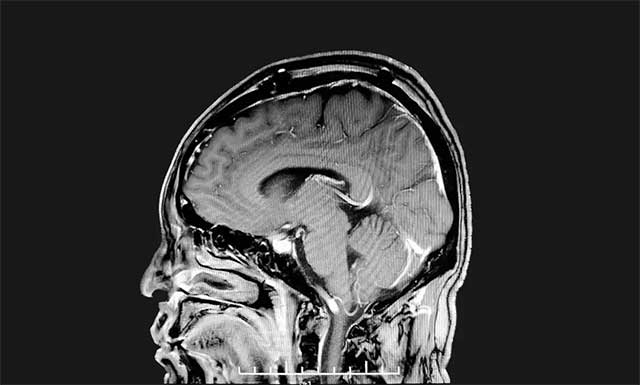

沈建康教授聚精会神、抽丝剥茧般一点点游离肿瘤包裹的静脉,再以超声刀切除残余肿瘤组织,历时四个多小时,手术顺利完成。术后经病理分析,该肿瘤为脑膜瘤,与术前诊断相一致。

▲ 肿瘤已被切除